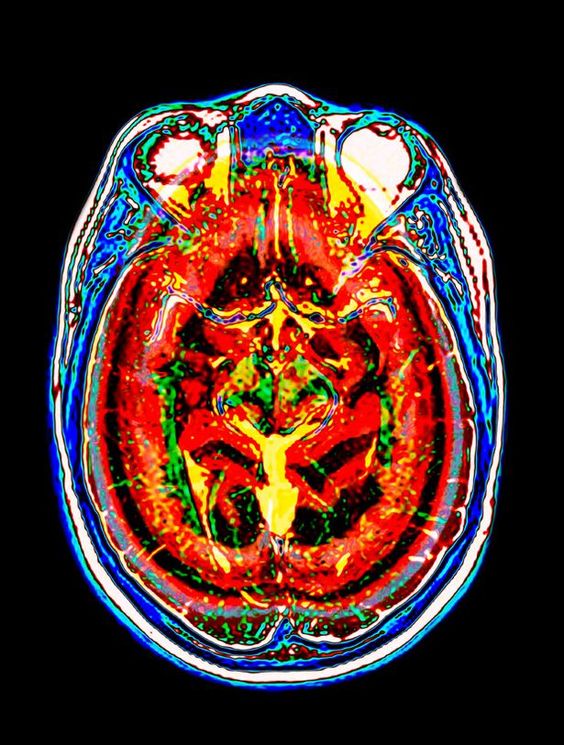

Підготовка до МРТ мозку

- Як правильно підготуватися до МРТ головного мозку

- Як роблять магнітно-резонансну томографію голови з контрастом

Як роблять магнітно-резонансну томографію голови з контрастом

Посилення видимості судин мозку досягається внутрішньовенною ін'єкцією гадолінію. Препарат робить артерії чутливими до магнітного поля. Парамагнетик є гіпоалергенним з'єднанням. Гіперчутливість на нього розвивається досить рідко. Перед контрастуванням слід виключити вагітність жінки.